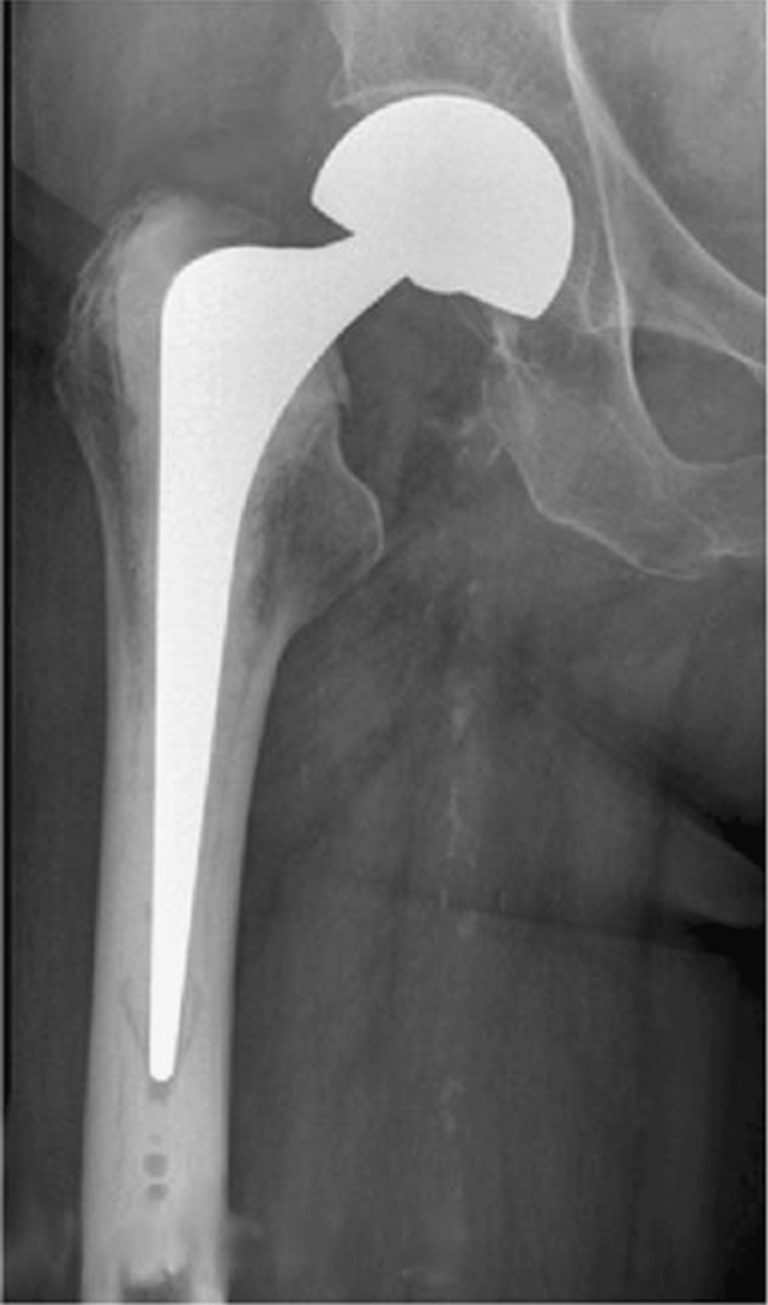

Anterior Approach Total Hip Replacement (AATHR) St. Surgical

Schematic diagram of a total hip replacement, indicating the different Hip Replacement Alternatives Stem Cell Sierra describes it as a process similar to an organ or tissue transplant but without the need for immunosuppression to avoid rejection. When we see an advanced case of osteoarthritis or a patient after normal prolotherapy has not met. Unlike invasive procedures like hip replacement surgery, stem cell therapy provides a viable alternative with minimal recovery time required. Stem cells,. Hip Replacement Alternatives Stem Cell.